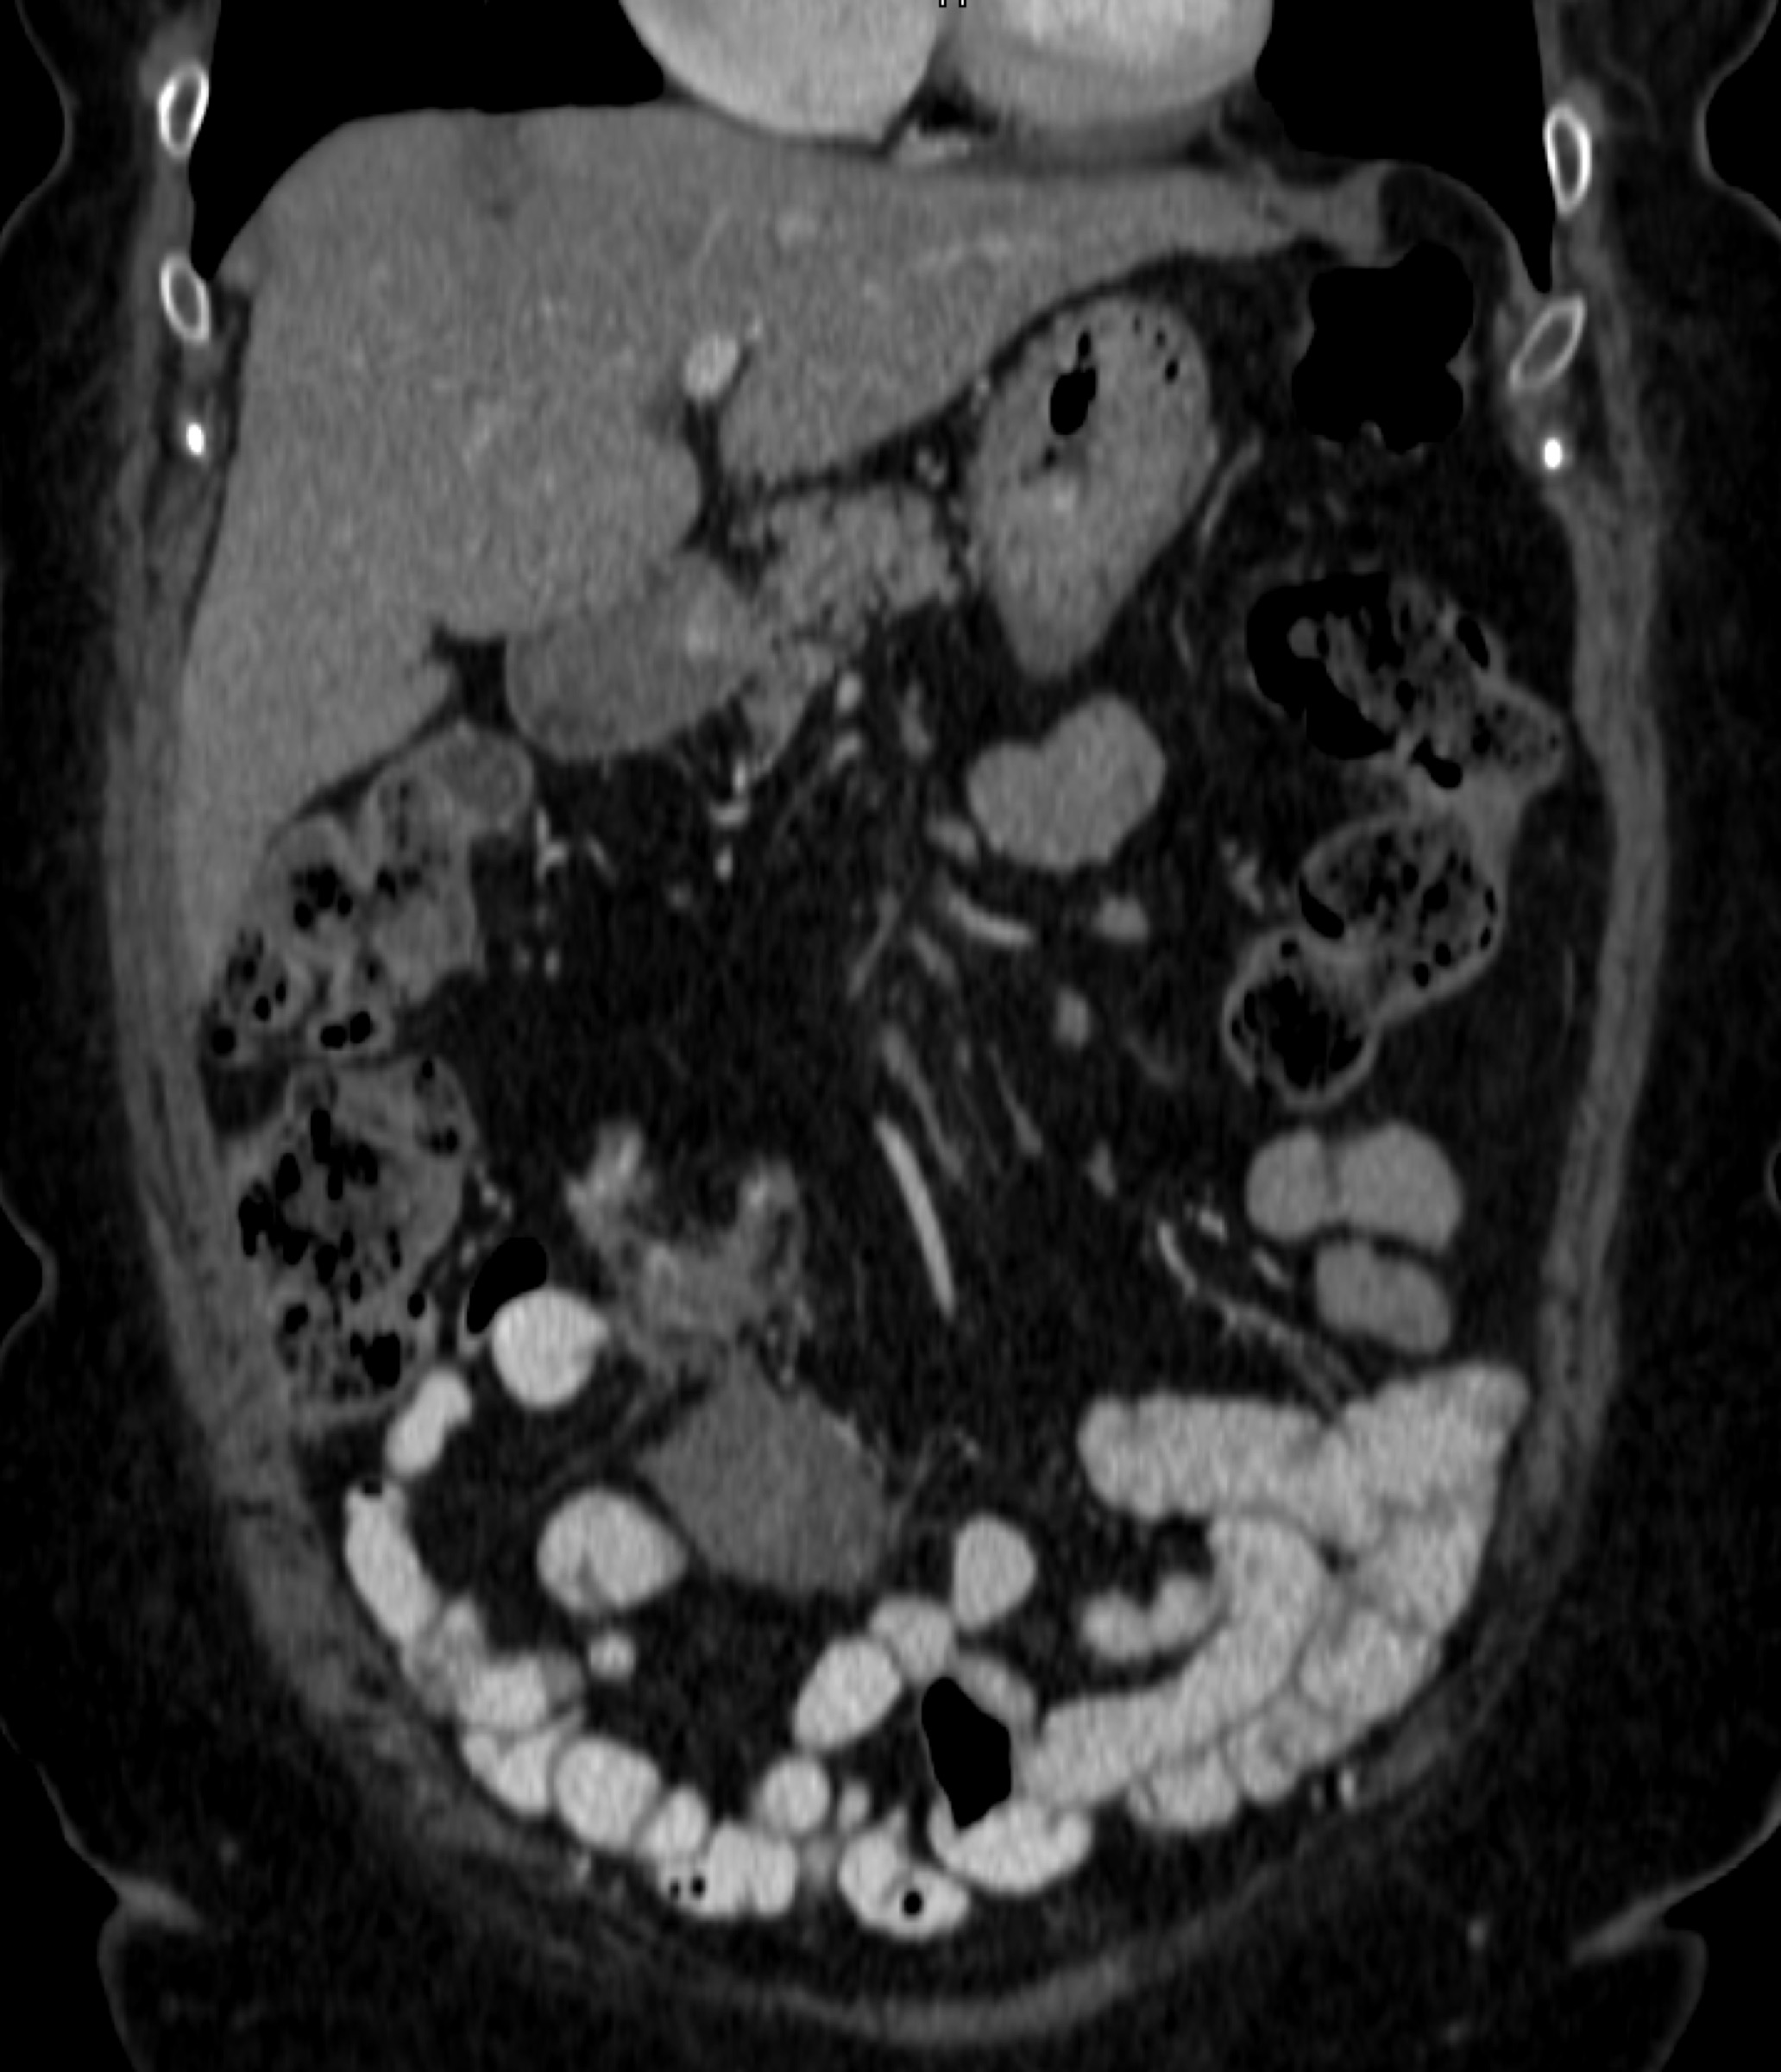

8) The most likely diagnosis in this case is?

clear cell renal cell carcinoma

large B-cell lymphoma

seminoma

renal abscess